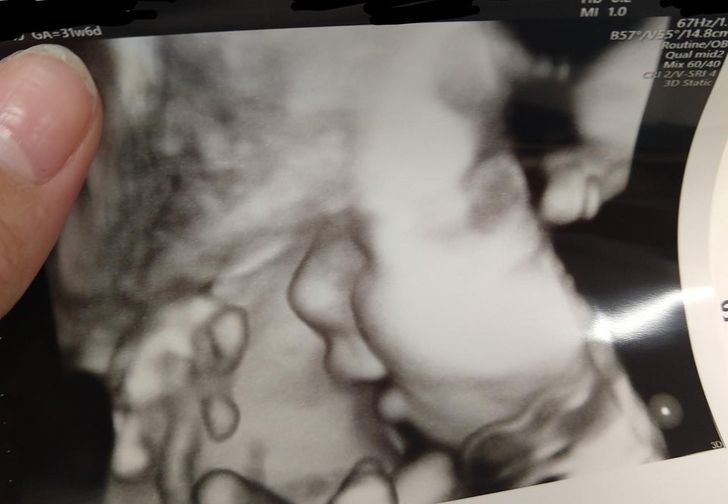

«Моя перша вагітність виявилася невдалою, і коли я дізналася, що знову чекаю дитину, дуже хвилювалася. Вчора на УЗД мій син усміхнувся, і тепер я готова плакати від щастя»